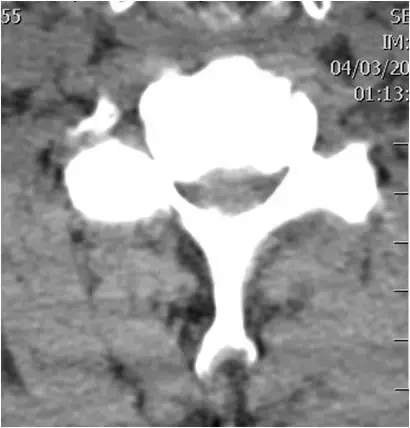

图29:颈椎的CT扫描。轴向截面。椎间盘突出。硬膜囊受压。

图30:颈椎的CT扫描。图29骨窗,轴向截面。椎间盘突出。硬膜囊受压。